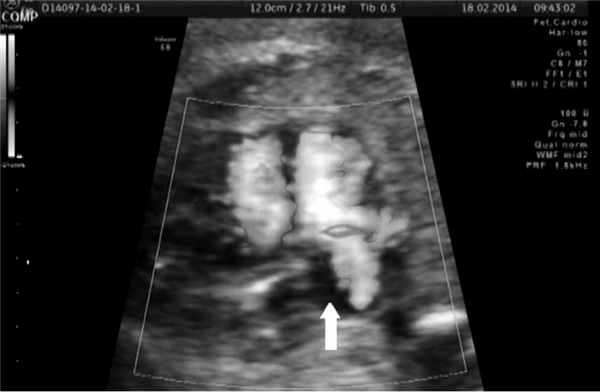

В 30 нед беременности нами совместно с сосудистым хирургом под постоянным ультразвуковым контролем проведена внутриутробная вальвулопластика овального окна. Через правое предсердие введен проводник в полость левого предсердия, а затем стандартный коронарный дилатационный баллонный катетер MINI TREK 2,0 × 12 мм (рис. 3).

Рис. 4. Эхокардиограмма пациентки П., 30 нед беременности. ГЛОС, открытое овальное окно после вальвулопластики.